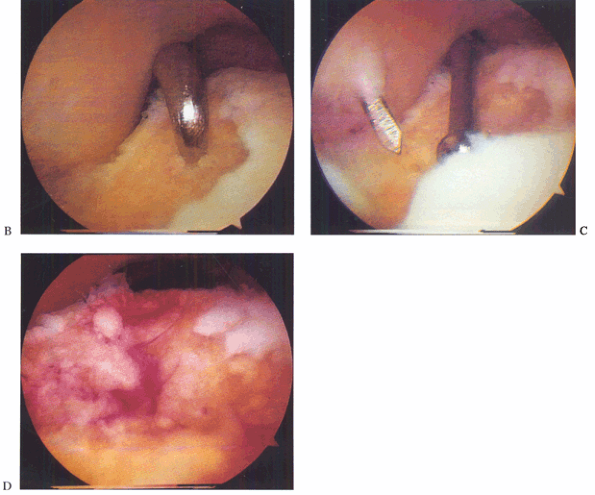

Figure 93.14. B: Microfracture of the subchondral surface using an awl. C: Using a drill guide for transmalleolar drilling of the subchondral bone. D:

The result of the above two treatments is a bleeding bone surface providing vascular access for cartilage formation. (This figure is printed in black and white as Figure 14 of Chapter 93.) |

Figure 93.15. B: Arthroscopic view from a posterior portal shows the inside of the osteochondral lesion and depth. C: Arthroscopic bone grafting is performed via an osteochondral transplant cylinder. D:

Arthroscopic view from a posterior portal of the bone graft filling the cyst near completion. (This figure is printed in black and white as Figure 15 of Chapter 93.) |